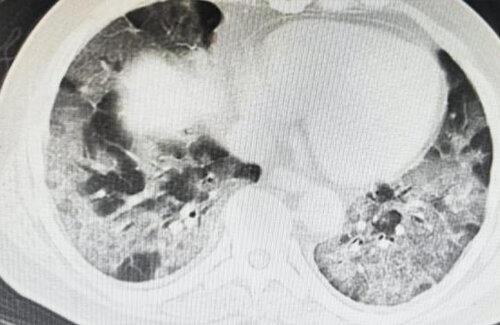

すごニュー 【強毒性変異株?】中国の医師「患者の半数が白肺」上海市民「白肺になっている若者が非常に多い。熱はないが全部白肺になっている」 lifecm03 2022年12月31日 1 分の読み取り 0 コメント 続きを読む Source: はちま起稿 contents About The Authorlifecm03 About The Author lifecm03 See author's posts 投稿ナビゲーション 前: 【悲報】ネットでおせちを注文した人、とんでもない置き配されて泣くwwwww次へ: 【悲報】ブラマヨ吉田さん、ワクチンを推奨する医師を「フナムシ」と呼んでしまう 誹謗中傷ではないかと話題に コメントを残す コメントをキャンセルメールアドレスが公開されることはありません。 ※ が付いている欄は必須項目ですコメント ※ 名前 ※ メール ※ サイト 次回のコメントで使用するためブラウザーに自分の名前、メールアドレス、サイトを保存する。 Δ 関連記事 すごニュー 『Amazon新生活セール』開催!新生活に必要な物が激安!厳選してピックアップしたからチェックしとけよ!!! lifecm03 2026年3月9日 0 すごニュー 『令和の虎』で医学部に行きたいという女子高生が100万円ゲット → この女子高生のヤバすぎる過去が判明して炎上・・・ lifecm03 2026年3月7日 0 すごニュー 『モンハンワイルズ』40fps固定にすると弓の貫通ビンが超強化されることが判明!弓使いに衝撃走る lifecm03 2026年3月7日 0